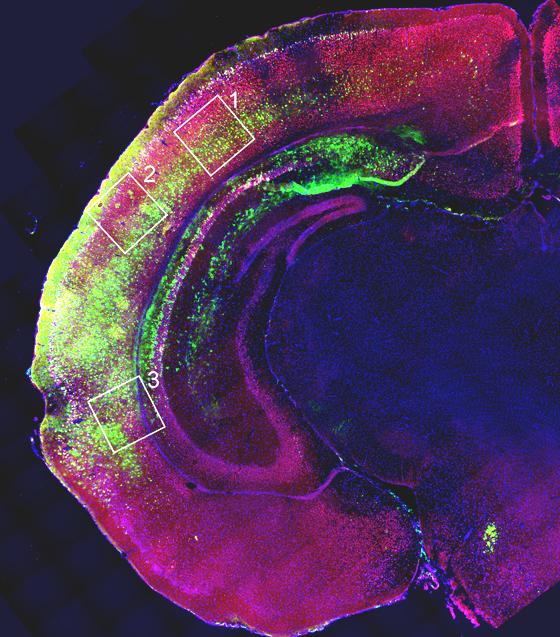

The team ran several tests. First, in vitro, the scientists checked whether stimulation through promoter RNA was able to amplify gene activity only where it was needed. "FOXG1 is only active in the anterior brain and we absolutely don't want it to act elsewhere in the nervous system or the body", explains Mallamaci. "The tests gave positive results: after stimulation, the gene continued to be expressed only in cells where it had previously been active and remained silent in tissues where it normally doesn't work. Very importantly, the activity observed increased by a factor not far from 2, i.e. that "double" expression that we were trying to achieve".